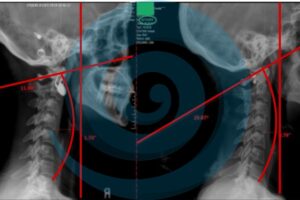

symptoms an upper cervical misalignment

Feel Bad Even When Your Imaging Looks Normal